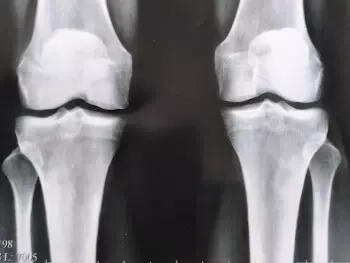

Поїхала в районну лікарню до Львова, там мені зробили недешеве обстеження. Через кілька годин результати були готові, і мій лікар сказав: “Чому ви ігнорували симптоми раніше? У вас артроз! Ви його запустили до 2 стадії. Якщо хочете не стати інвалідом, вам потрібно робити операцію на стегні та колінах!”

(ренген знімки моїх колінних та тазових суглобів)